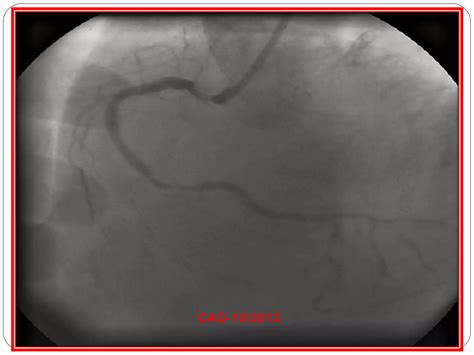

• Cardiac Catheterization: This invasive procedure involves inserting a catheter into the heart to measure pressure and blood flow, and to visualize the coronary arteries.

• Coronary Artery Disease: This condition occurs when the arteries that supply blood to the heart become narrowed or blocked due to the buildup of plaque.